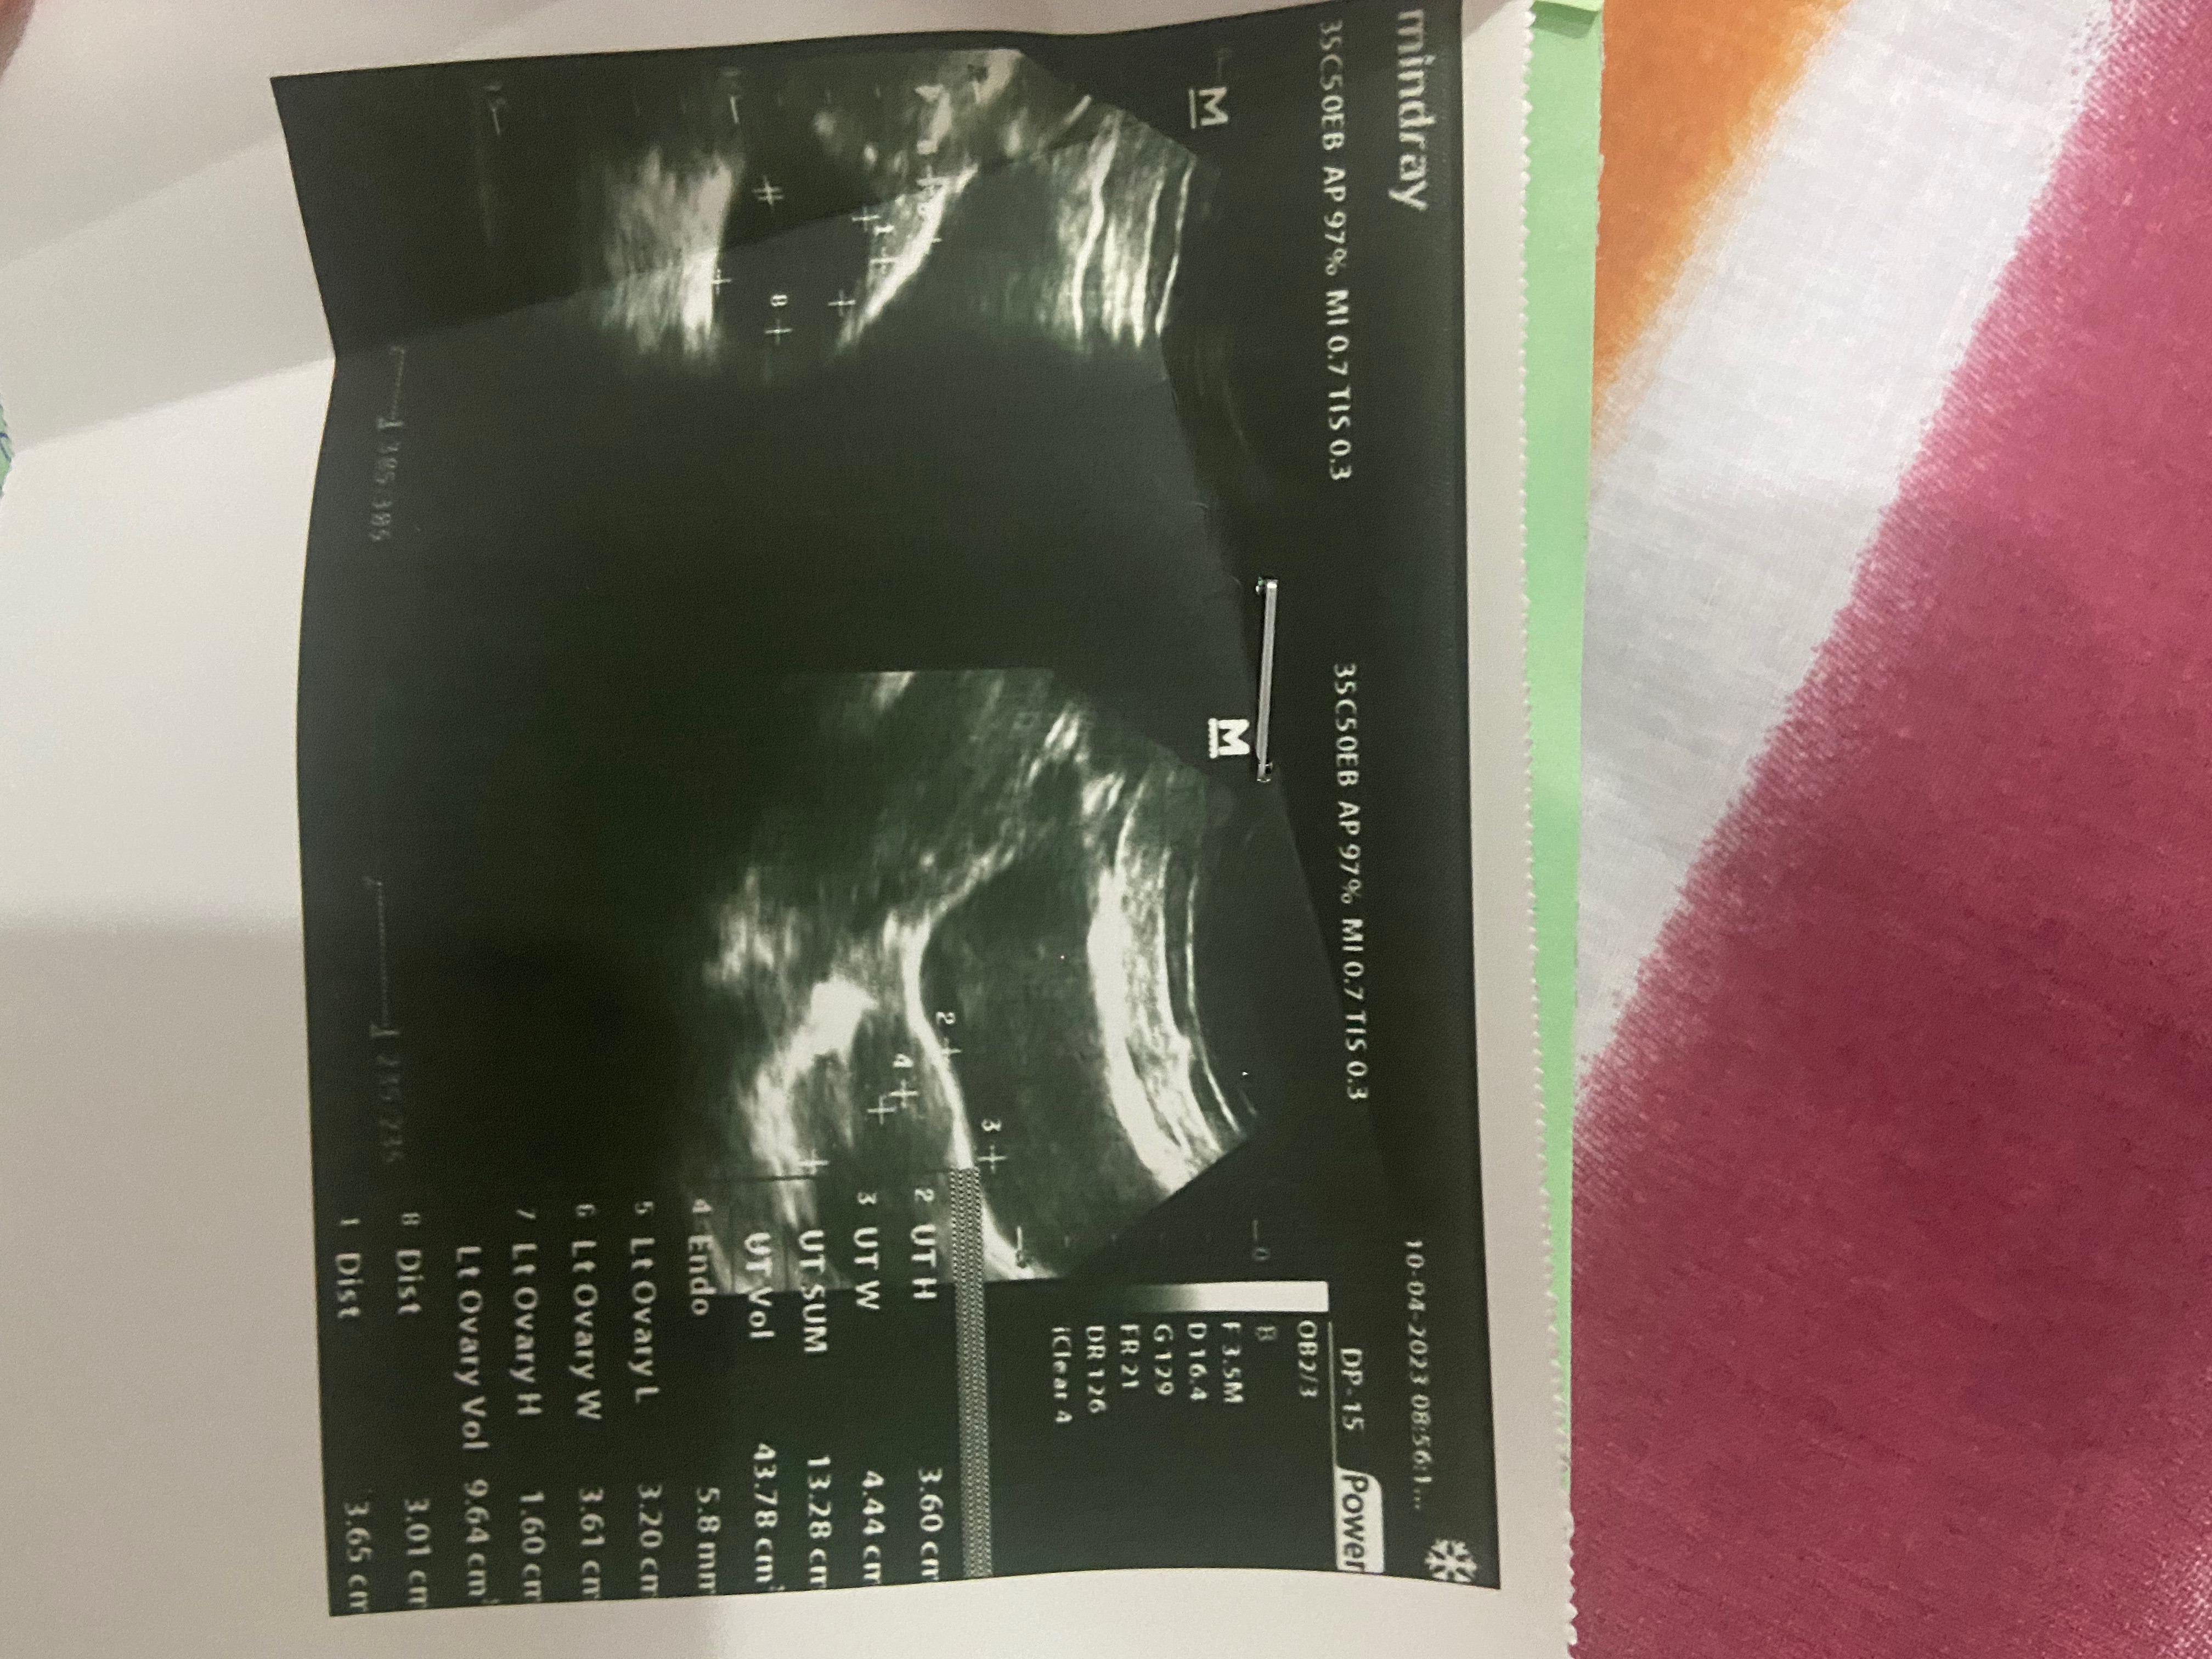

Need ultrasound of cyst. If it is clear cyst. Usually it will resilve in 3-6 months

Ultrasound report

need ultrasound report